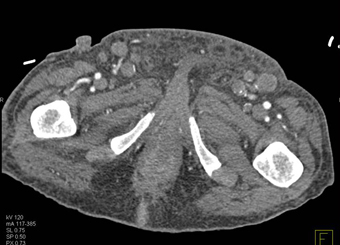

In this patient with known colon cancer the soft tissue masses are most likely

metastatic colon cancer to the subcutaneous tissue